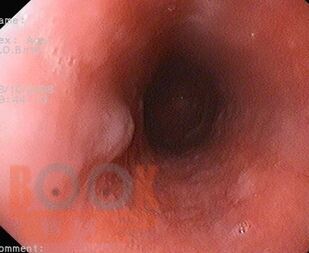

Изображения эндоскопических изменений при внекишечных заболеваниях

Монография посвящена желудочно-кишечным проявлениям при системных и внекишечных заболеваниях. В ней систематизированы данные о клинических, эндоскопических и морфологических изменениях ЖКТ, возникающих на фоне кожных, иммунологических, сердечно-сосудистых, легочных, почечных, метаболических, эндокринных, гематологических, неврологических и ревматологических заболеваний, а также при беременности, гинекологических состояниях и пищевой аллергии.

Отдельно рассмотрены механизмы поражения (общие патогенетические пути, функциональные нарушения, лекарственные осложнения) и практические подходы к диагностике и лечению.